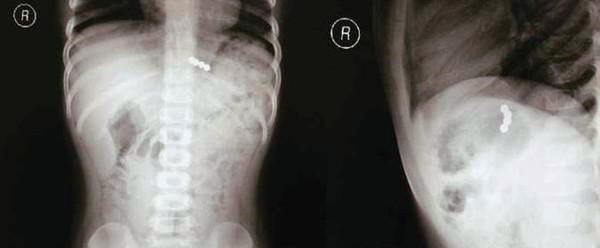

(网络图,巴克球被吞入体内的X光片)

记者了解到,原来,事件起因是这位家长买了一盒巴克球给2岁的儿子玩耍。在家长没有留意时,孩子不慎将其中5颗巴克球吞了下去,结果这个5颗巴克球在孩子的肠子里相互吸引,导致肠子重叠,相互压迫穿破。紧急将孩子送到医院后,经过医生紧急手术,开腹后取出。